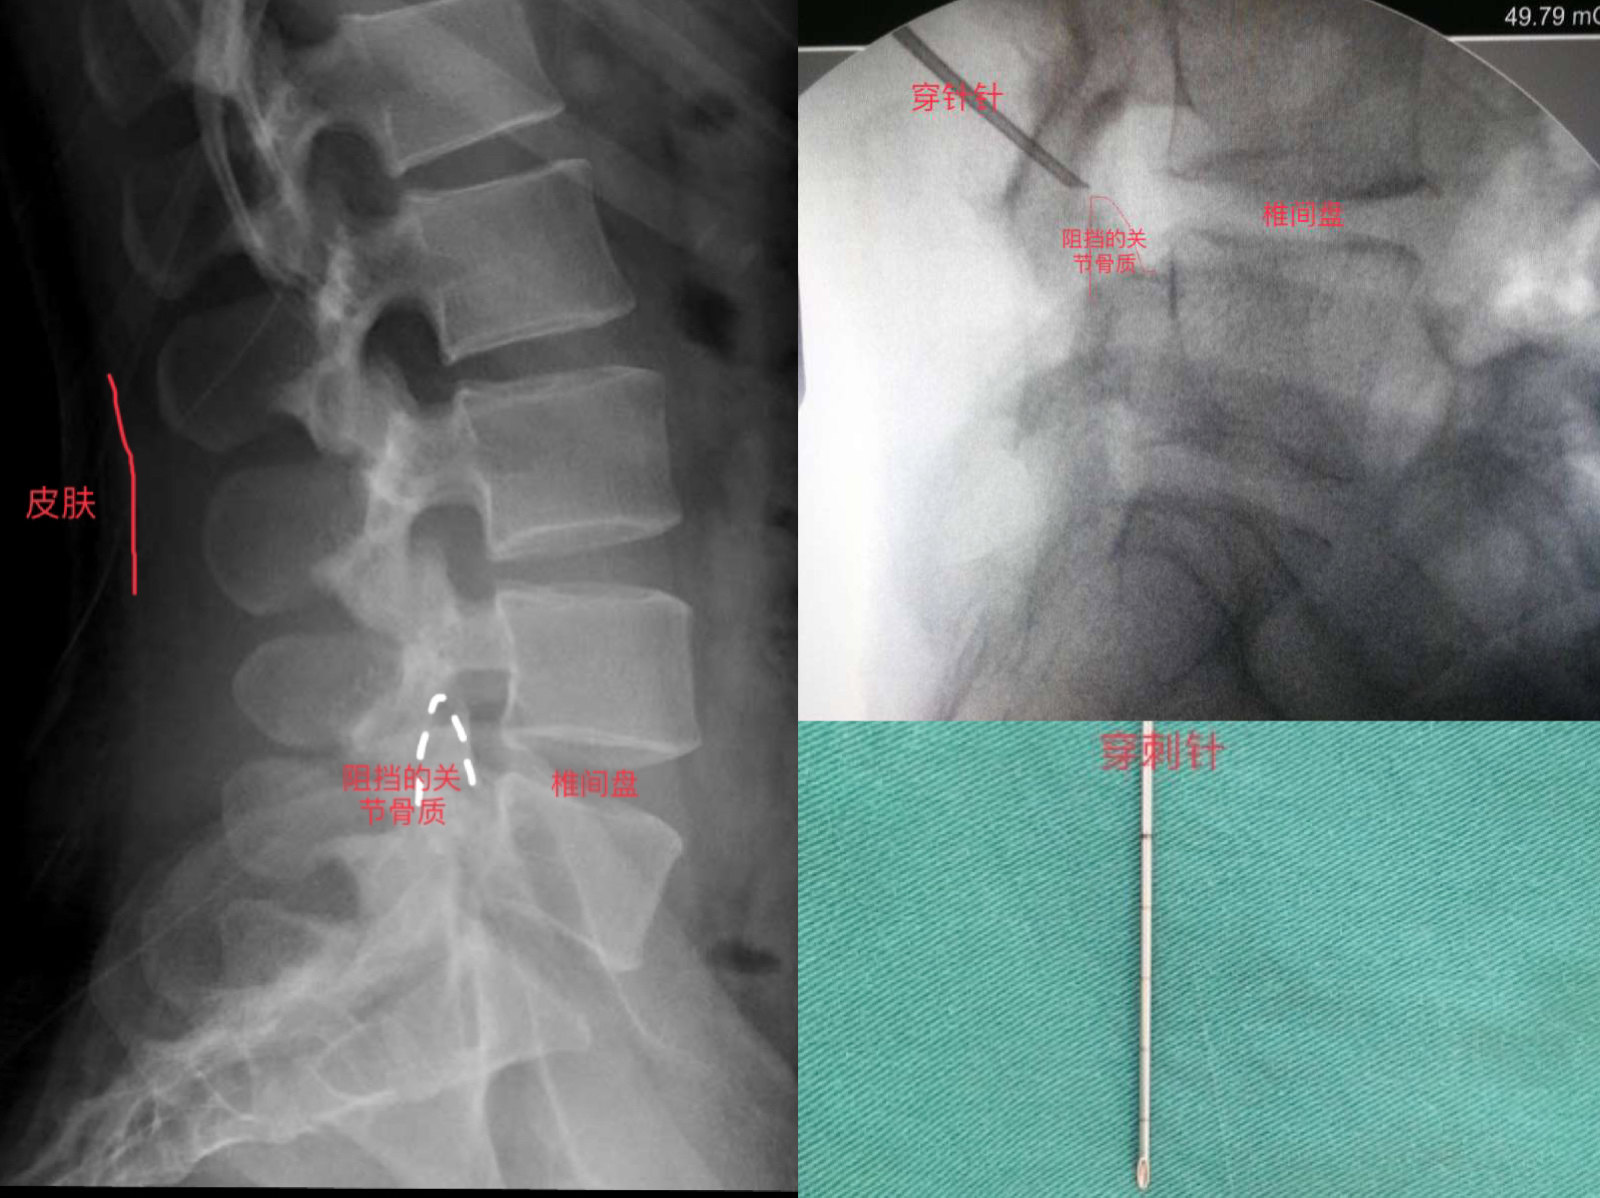

穿刺

打完麻药后手术就正式开始,我们会选用非常细的穿刺针从皮肤进针点穿刺到突出椎间盘,但是穿刺过程中会有椎间孔区的关节骨质阻挡,所以我们常规就将穿刺针顶到阻挡的关节骨质表面,然后用器械去除阻挡的骨质。见下图。

关节去骨成型

穿刺过程由于关节骨质阻挡,无法顺利到达椎间盘,因此穿刺针顶到阻挡的骨质后,我们会用器械去掉阻挡的骨质。去掉的骨质总体量很小,对身体无影响。